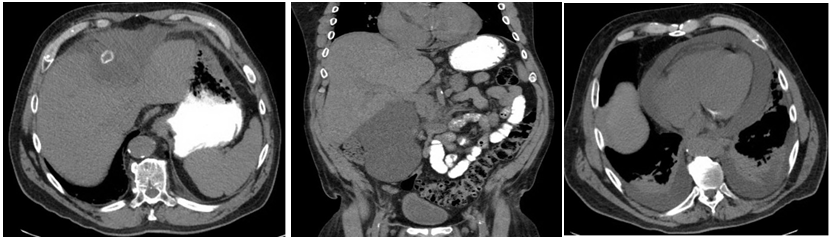

Due to concerns for a fistulous communication between the pericardial and peritoneal cavities, the procedure was begun in the chest first to reduce the chances of cardiac tamponade from pneumopericardium. A subxyphoid pericardial window was performed and a 32fr chest tube was placed. On laparoscopy, significant adhesions were noted above the liver (Figure 3). Dissection above the liver was challenging given the chronic inflammation and the proximity of the abscess cavity to the hepatic veins. The abscess cavity in the sub diaphragmatic space was entered and the stone was found (Figure 4). The remnant abscess was drained and a flat Jackson Pratt drain was left in the cavity after irrigation. The stone was retrieved using an end catch bag (Figure 5). The patient’s postoperative recovery was uneventful. The pericardial drain was removed prior to discharge and his abdominal drain was removed in clinic. He was sent home with a 2week course of ceftriaxone.

Figure 4 The abscess cavity in the sub diaphragmatic space was entered and the stone was found.

Figure 5 The stone was retrieved using an end catch bag.